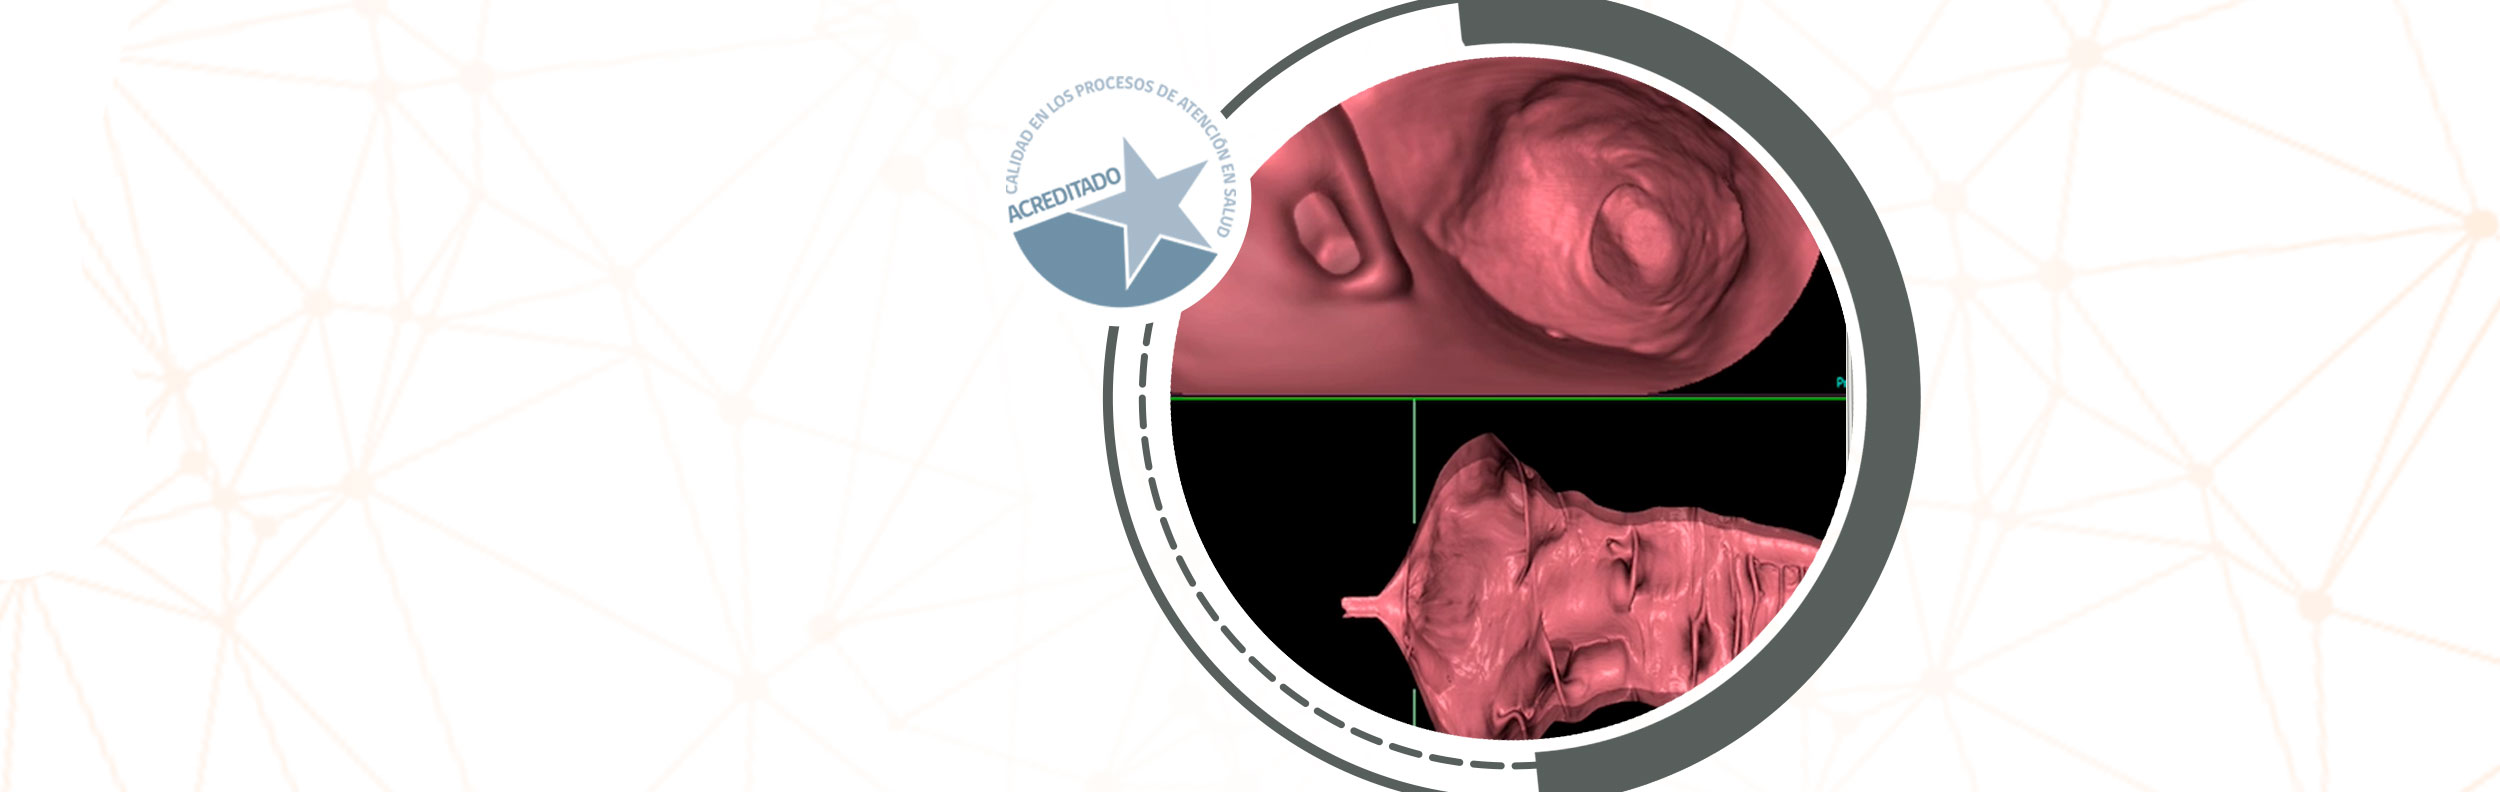

Centro especializado de Imagenología

En el diagnóstico de la mayoría de las enfermedades, el apoyo que entregan los exámenes por imágenes es fundamental. Médicos de las más diversas especialidades requieren de un centro especializado y avanzado en imagen médica de alta calidad que actúe con rapidez y seguridad para definir el tratamiento apropiado para sus pacientes.

Nacemos en la ciudad de Rancagua como uno de los centros de imagenología más modernos de la región de O'Higgins. Ofrecemos una amplia gama de servicios de exámenes con tecnología de vanguardia, incluyendo TAC de 128 canales, Resonancia Magnética de 3 Teslas y PET-CT.

Nuestro compromiso con la mejora continua en la calidad de las imágenes y nuestra capacidad médico-técnica nos permite ofrecer diagnósticos más precisos, beneficiando tanto a médicos especialistas como a nuestros pacientes. Como referentes en diagnóstico médico, somos el único centro acreditado de la región en procesos de atención en salud en imagenología médica.